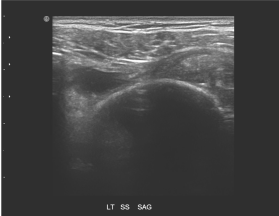

72.

85歲女性患者,主訴左肩疼痛超過6個月,有局部壓痛,無肌肉萎縮現象,圖為左肩部超音波檢查,上圖為旋轉環帶長軸切 面,下圖為短軸切面,最可能之診斷為何? (A)風濕性關節炎(rheumatoid arthritis) (B)棘上肌腱斷裂(supraspinatus tendon tear) (C)化膿性關節炎(pyogenic arthritis) (D)肩三角肌撕裂(deltoid muscle tear)